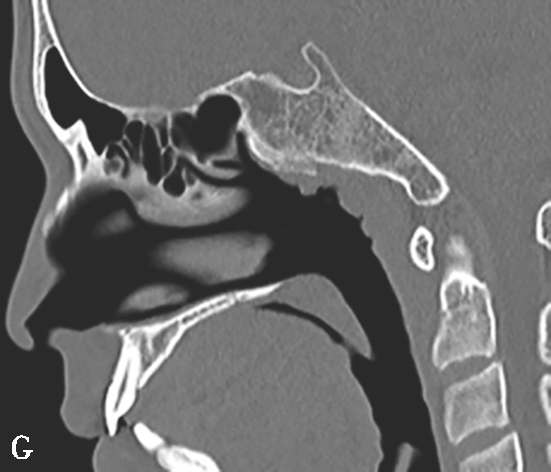

蝶窦常见解剖变异包括:①有分隔的蝶窦,可为纤维或骨性分隔分成几个不对称的部分,此变异容易导致蝶窦手术引流不完全而残留病变;②介甲型蝶窦,窦腔略有气化,发育很小,窦腔后缘与鞍结节垂直线之间尚有10mm厚骨质;③鞍前型蝶窦,蝶窦发育较小,窦腔后缘与鞍结节垂直线相齐,恰好位于蝶鞍之前,蝶鞍底大部分为松质骨;④半鞍型蝶窦,发育尚好,后上缘占鞍底前半部;⑤全鞍型蝶窦,发育良好,自鞍结节至鞍背连线的全鞍底与蝶窦只一层薄骨板;⑥枕鞍型蝶窦,与全鞍型相似,但发育更大,后缘超过鞍背垂线,蝶窦侵入枕骨使斜坡骨板更薄(图1-3-7)。

图1-3-7 蝶窦及蝶窦区解剖变异

A.颈内动脉管突入蝶窦;B.蝶窦间隔(白箭);C.左侧翼突气化;D.蝶嵴(星)、蝶骨大翼(白箭)、鞍背气化(虚箭);E.蝶骨小翼气化(白箭);F、G.鞍前型蝶窦(三角);H、I.甲介型蝶窦;J、K.鞍型蝶窦;L.Odoni气房(白箭)